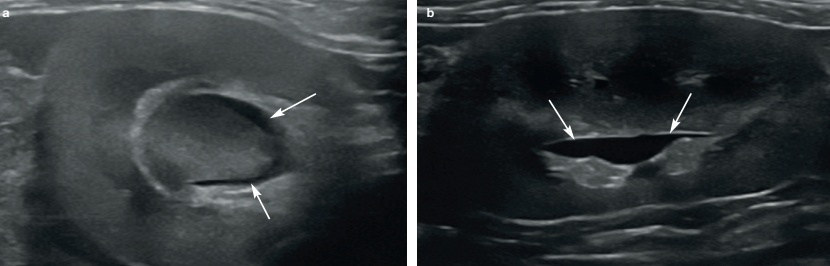

저에코성 혹은 무에코의 수질(medulla)을 확장된 신우로 혼동하지 않는 것이 중요합니다. 신우 확장은 보통 초음파 횡단면(transverse plane)에서 더 쉽게 보입니다. 신우 안의 액체는 심장 모양 또는 초승달 모양의 무에코성 부위로 보이며, 신장 능선(renal crest)을 감싸는 형태를 보입니다(그림 1).

신장을 배 측면(dorsal plane)으로 보면 신우 확장은 선형~타원형으로 보입니다. 확장이 점점 심해지면 신우는 둥근 모양을 나타냅니다(그림 2).